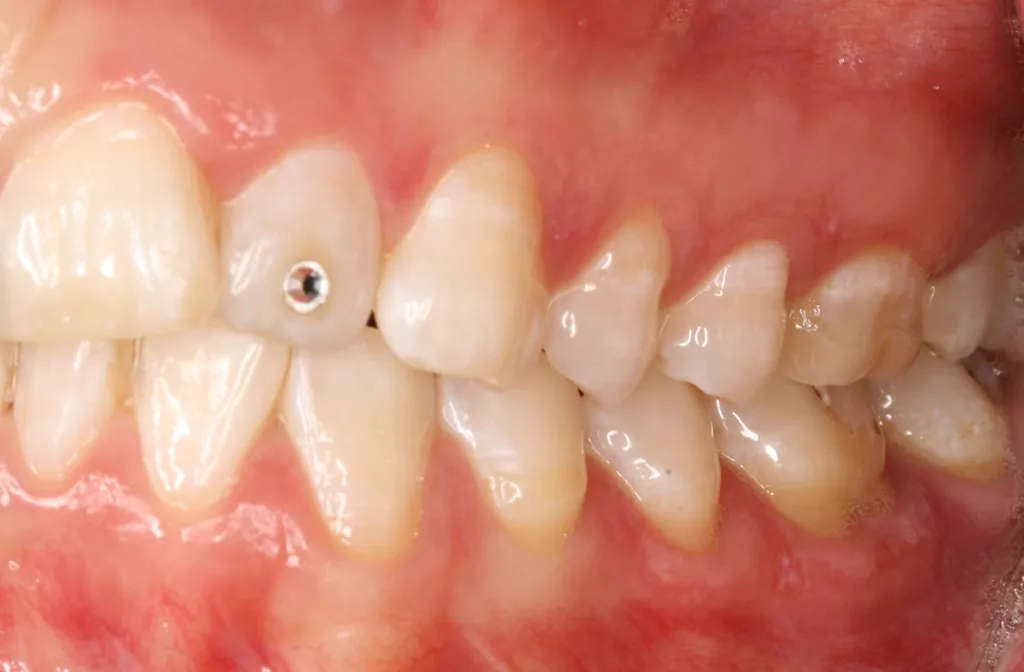

![Abb. 3a: Klinische Dokumentation einer 24-jährigen Patientin mit einer weit fortgeschrittenen lokalen parodontalen Destruktion, die mit großer Wahrscheinlichkeit durch ein Zungenpiercing hervorgerufen wurde [10]. Mit Ausnahme der Symptomatik im Unterkiefer-Frontzahnbereich wies die Patientin flache Sondierungstiefen und einzelne Regionen mit Gingivitis auf. Die Zähne reagierten positiv auf eine Sensibilitätsprobe mit Kältespray. Das Piercing war zum Zeitpunkt der Vorstellung in der Klinik bereits nicht mehr im Mund. Es wurde eine stufenweise systematische parodontale Therapie eingeleitet. Die verbliebenen und nahezu unveränderten erhöhten Son¬dierungstiefen wurden einem parodontal-chirurgischen Eingriff mit zusätzlichen, die Regenera¬tion fördernden Maßnahmen (Straumann Emdogain, Straumann, Basel, Schweiz) unterzogen. Es wurde die für diese Operationen empfohlene Schnittführung im Sinne eines Papillenerhaltungs¬lappens angewendet. Der nach der Degranulierung mit Hand- und Ultraschallinstrumenten sicht¬bare knöcherne Defekt wies eine ungünstige Morphologie für die Regeneration auf. Ein primärer Wundverschluss wurde dennoch erzielt. Diese Ansätze blieben letztendlich erfolglos und der Zahn 41 ging verloren (parodontologische Therapie gemeinsam mit Dr. L. Büttel, Basel, Schweiz).](https://dentalwelt.spitta.de/wp-content/uploads/2025/07/Abb-3a-1024x684.webp)

![Abb. 3b: Klinische Dokumentation einer 24-jährigen Patientin mit einer weit fortgeschrittenen lokalen parodontalen Destruktion, die mit großer Wahrscheinlichkeit durch ein Zungenpiercing hervorgerufen wurde [10]. Mit Ausnahme der Symptomatik im Unterkiefer-Frontzahnbereich wies die Patientin flache Sondierungstiefen und einzelne Regionen mit Gingivitis auf. Die Zähne reagierten positiv auf eine Sensibilitätsprobe mit Kältespray. Das Piercing war zum Zeitpunkt der Vorstellung in der Klinik bereits nicht mehr im Mund. Es wurde eine stufenweise systematische parodontale Therapie eingeleitet. Die verbliebenen und nahezu unveränderten erhöhten Son¬dierungstiefen wurden einem parodontal-chirurgischen Eingriff mit zusätzlichen, die Regenera¬tion fördernden Maßnahmen (Straumann Emdogain, Straumann, Basel, Schweiz) unterzogen. Es wurde die für diese Operationen empfohlene Schnittführung im Sinne eines Papillenerhaltungs¬lappens angewendet. Der nach der Degranulierung mit Hand- und Ultraschallinstrumenten sicht¬bare knöcherne Defekt wies eine ungünstige Morphologie für die Regeneration auf. Ein primärer Wundverschluss wurde dennoch erzielt. Diese Ansätze blieben letztendlich erfolglos und der Zahn 41 ging verloren (parodontologische Therapie gemeinsam mit Dr. L. Büttel, Basel, Schweiz).](https://dentalwelt.spitta.de/wp-content/uploads/2025/07/Abb-3b-1024x684.webp)

![Abb. 3c: Klinische Dokumentation einer 24-jährigen Patientin mit einer weit fortgeschrittenen lokalen parodontalen Destruktion, die mit großer Wahrscheinlichkeit durch ein Zungenpiercing hervorgerufen wurde [10]. Mit Ausnahme der Symptomatik im Unterkiefer-Frontzahnbereich wies die Patientin flache Sondierungstiefen und einzelne Regionen mit Gingivitis auf. Die Zähne reagierten positiv auf eine Sensibilitätsprobe mit Kältespray. Das Piercing war zum Zeitpunkt der Vorstellung in der Klinik bereits nicht mehr im Mund. Es wurde eine stufenweise systematische parodontale Therapie eingeleitet. Die verbliebenen und nahezu unveränderten erhöhten Son¬dierungstiefen wurden einem parodontal-chirurgischen Eingriff mit zusätzlichen, die Regenera¬tion fördernden Maßnahmen (Straumann Emdogain, Straumann, Basel, Schweiz) unterzogen. Es wurde die für diese Operationen empfohlene Schnittführung im Sinne eines Papillenerhaltungs¬lappens angewendet. Der nach der Degranulierung mit Hand- und Ultraschallinstrumenten sicht¬bare knöcherne Defekt wies eine ungünstige Morphologie für die Regeneration auf. Ein primärer Wundverschluss wurde dennoch erzielt. Diese Ansätze blieben letztendlich erfolglos und der Zahn 41 ging verloren (parodontologische Therapie gemeinsam mit Dr. L. Büttel, Basel, Schweiz).](https://dentalwelt.spitta.de/wp-content/uploads/2025/07/Abb-3c-1024x722.webp)

![Abb. 3d: Klinische Dokumentation einer 24-jährigen Patientin mit einer weit fortgeschrittenen lokalen parodontalen Destruktion, die mit großer Wahrscheinlichkeit durch ein Zungenpiercing hervorgerufen wurde [10]. Mit Ausnahme der Symptomatik im Unterkiefer-Frontzahnbereich wies die Patientin flache Sondierungstiefen und einzelne Regionen mit Gingivitis auf. Die Zähne reagierten positiv auf eine Sensibilitätsprobe mit Kältespray. Das Piercing war zum Zeitpunkt der Vorstellung in der Klinik bereits nicht mehr im Mund. Es wurde eine stufenweise systematische parodontale Therapie eingeleitet. Die verbliebenen und nahezu unveränderten erhöhten Son¬dierungstiefen wurden einem parodontal-chirurgischen Eingriff mit zusätzlichen, die Regenera¬tion fördernden Maßnahmen (Straumann Emdogain, Straumann, Basel, Schweiz) unterzogen. Es wurde die für diese Operationen empfohlene Schnittführung im Sinne eines Papillenerhaltungs¬lappens angewendet. Der nach der Degranulierung mit Hand- und Ultraschallinstrumenten sicht¬bare knöcherne Defekt wies eine ungünstige Morphologie für die Regeneration auf. Ein primärer Wundverschluss wurde dennoch erzielt. Diese Ansätze blieben letztendlich erfolglos und der Zahn 41 ging verloren (parodontologische Therapie gemeinsam mit Dr. L. Büttel, Basel, Schweiz).](https://dentalwelt.spitta.de/wp-content/uploads/2025/07/Abb-3d-1024x665.webp)

Wir sind vor mittlerweile 17 Jahren erstmals mit der Frage etwaiger Auswirkungen oraler Piercings auf den Zahnhalteapparat konfrontiert worden [10]. Eine damals 24-jährige Patientin stellte sich mit einem ungewöhnlichen Befund vor (Abb. 3a bis d). Bei sonst parodontal unauffälligen Verhältnissen mit Sondierungstiefen zwischen 2 und 3 mm, reichten die Sondierungstiefen an den Schneidezähnen im Unterkiefer bis 12 mm. Zahn 41 schmerzte und wies eine erhöhte Lockerung von Grad 2 auf. Bukkal war zudem eine Fistel mit Pusentleerung zu detektieren. Die Patientin war allgemeinmedizinisch gesund, rauchte nicht und hatte auch keinen Diabetes mellitus. Eine familiäre Prädisposition für parodontale Erkrankungen ließ sich anamnestisch nicht konstruieren. Die Mundhygiene war zwar nicht perfekt, stand aber auch in keinem Verhältnis zu ihrem dramatischen lokalen parodontalen Befund. Im Rahmen der anamnestischen Befragung, fokussiert auf ungewöhnliche Habits, berichtete die Patientin, bis vor kurzem ein Zungenpiercing getragen zu haben, dieses aber vor ca. sechs Monaten entfernt zu haben. Die Piercing-Tragedauer betrug etwa drei Jahre.

In der Gesamtschau der zusammengetragenen Daten und unter Berücksichtigung der in medizinischen Datenbanken aufgefundenen einzelnen Fallbeschreibungen erschien uns die wahrscheinlichste Ursache für den vorliegenden Befund tatsächlich das Zungenpiercing zu sein [11]. Die parodontale nicht-chirurgische, wie auch die chirurgisch-regenerative Therapie waren nicht erfolgreich und die Patientin verlor den stark kompromittierten Unterkiefer-Frontzahn. Seit dieser Zeit beschäftigen wir uns intensiver mit diesem Thema. So begannen wir mit der Sammlung und Erfassung der klinischen Parameter bei Patienten/-innen, die ein orales Piercing tragen oder einst trugen. Die Ergebnisse wurden zunächst im Rahmen einer Masterarbeit ausgewertet, als Posterbeitrag bei der Europerio 9 in Amsterdam veröffentlicht und später dann als Manuskript publiziert [10,12].